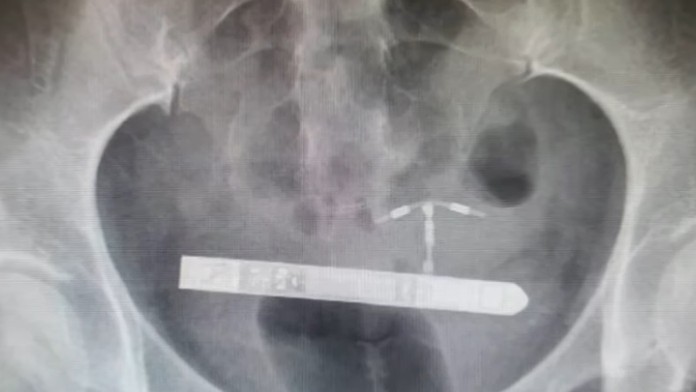

Následne požiadali o pomoc gynekológa Grega Marchanda. Ten bol ohromený, keď röntgen odhalil, že vibrátor sa nachádza močovom mechúre. "Nič podobne som nikdy nevidel," povedal špecialista.

Doktor dodal, že vibrátor jej nejako prešiel močovou trubicou, a tak ho museli chirurgicky odstrániť.